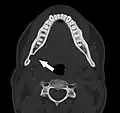

Stafne bone cavity seen on axial CT Stafne bone cavity seen on axial CT